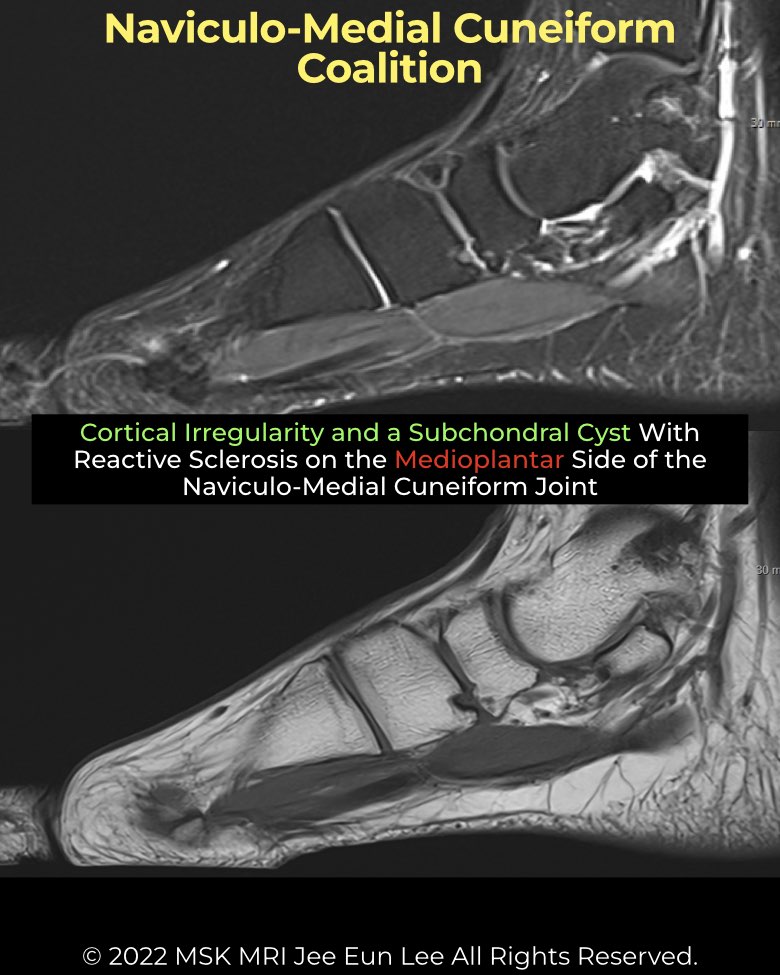

A naviculo–medial cuneiform (NC) coalition is a rare congenital union of the navicular and medial cuneiform, usually fibrocartilaginous or cartilaginous. Unlike calcaneonavicular or talocalcaneal types (~90% of cases), this midfoot coalition is less familiar but may be more common than expected.

- Imaging Findings:

• Location – plantar NC joint.

• Plain films/CT – irregular articular surface (97%), subchondral sclerosis (86%), cysts (83%), joint space narrowing (69%), beak-like medial spur (66%).

• MRI – low T1 / high T2 signal bridging at plantar margin; marrow edema may be present. - Differential: Can mimic OA, but coalition typically involves the plantar margin, whereas OA changes are more dorsal with large spurs.